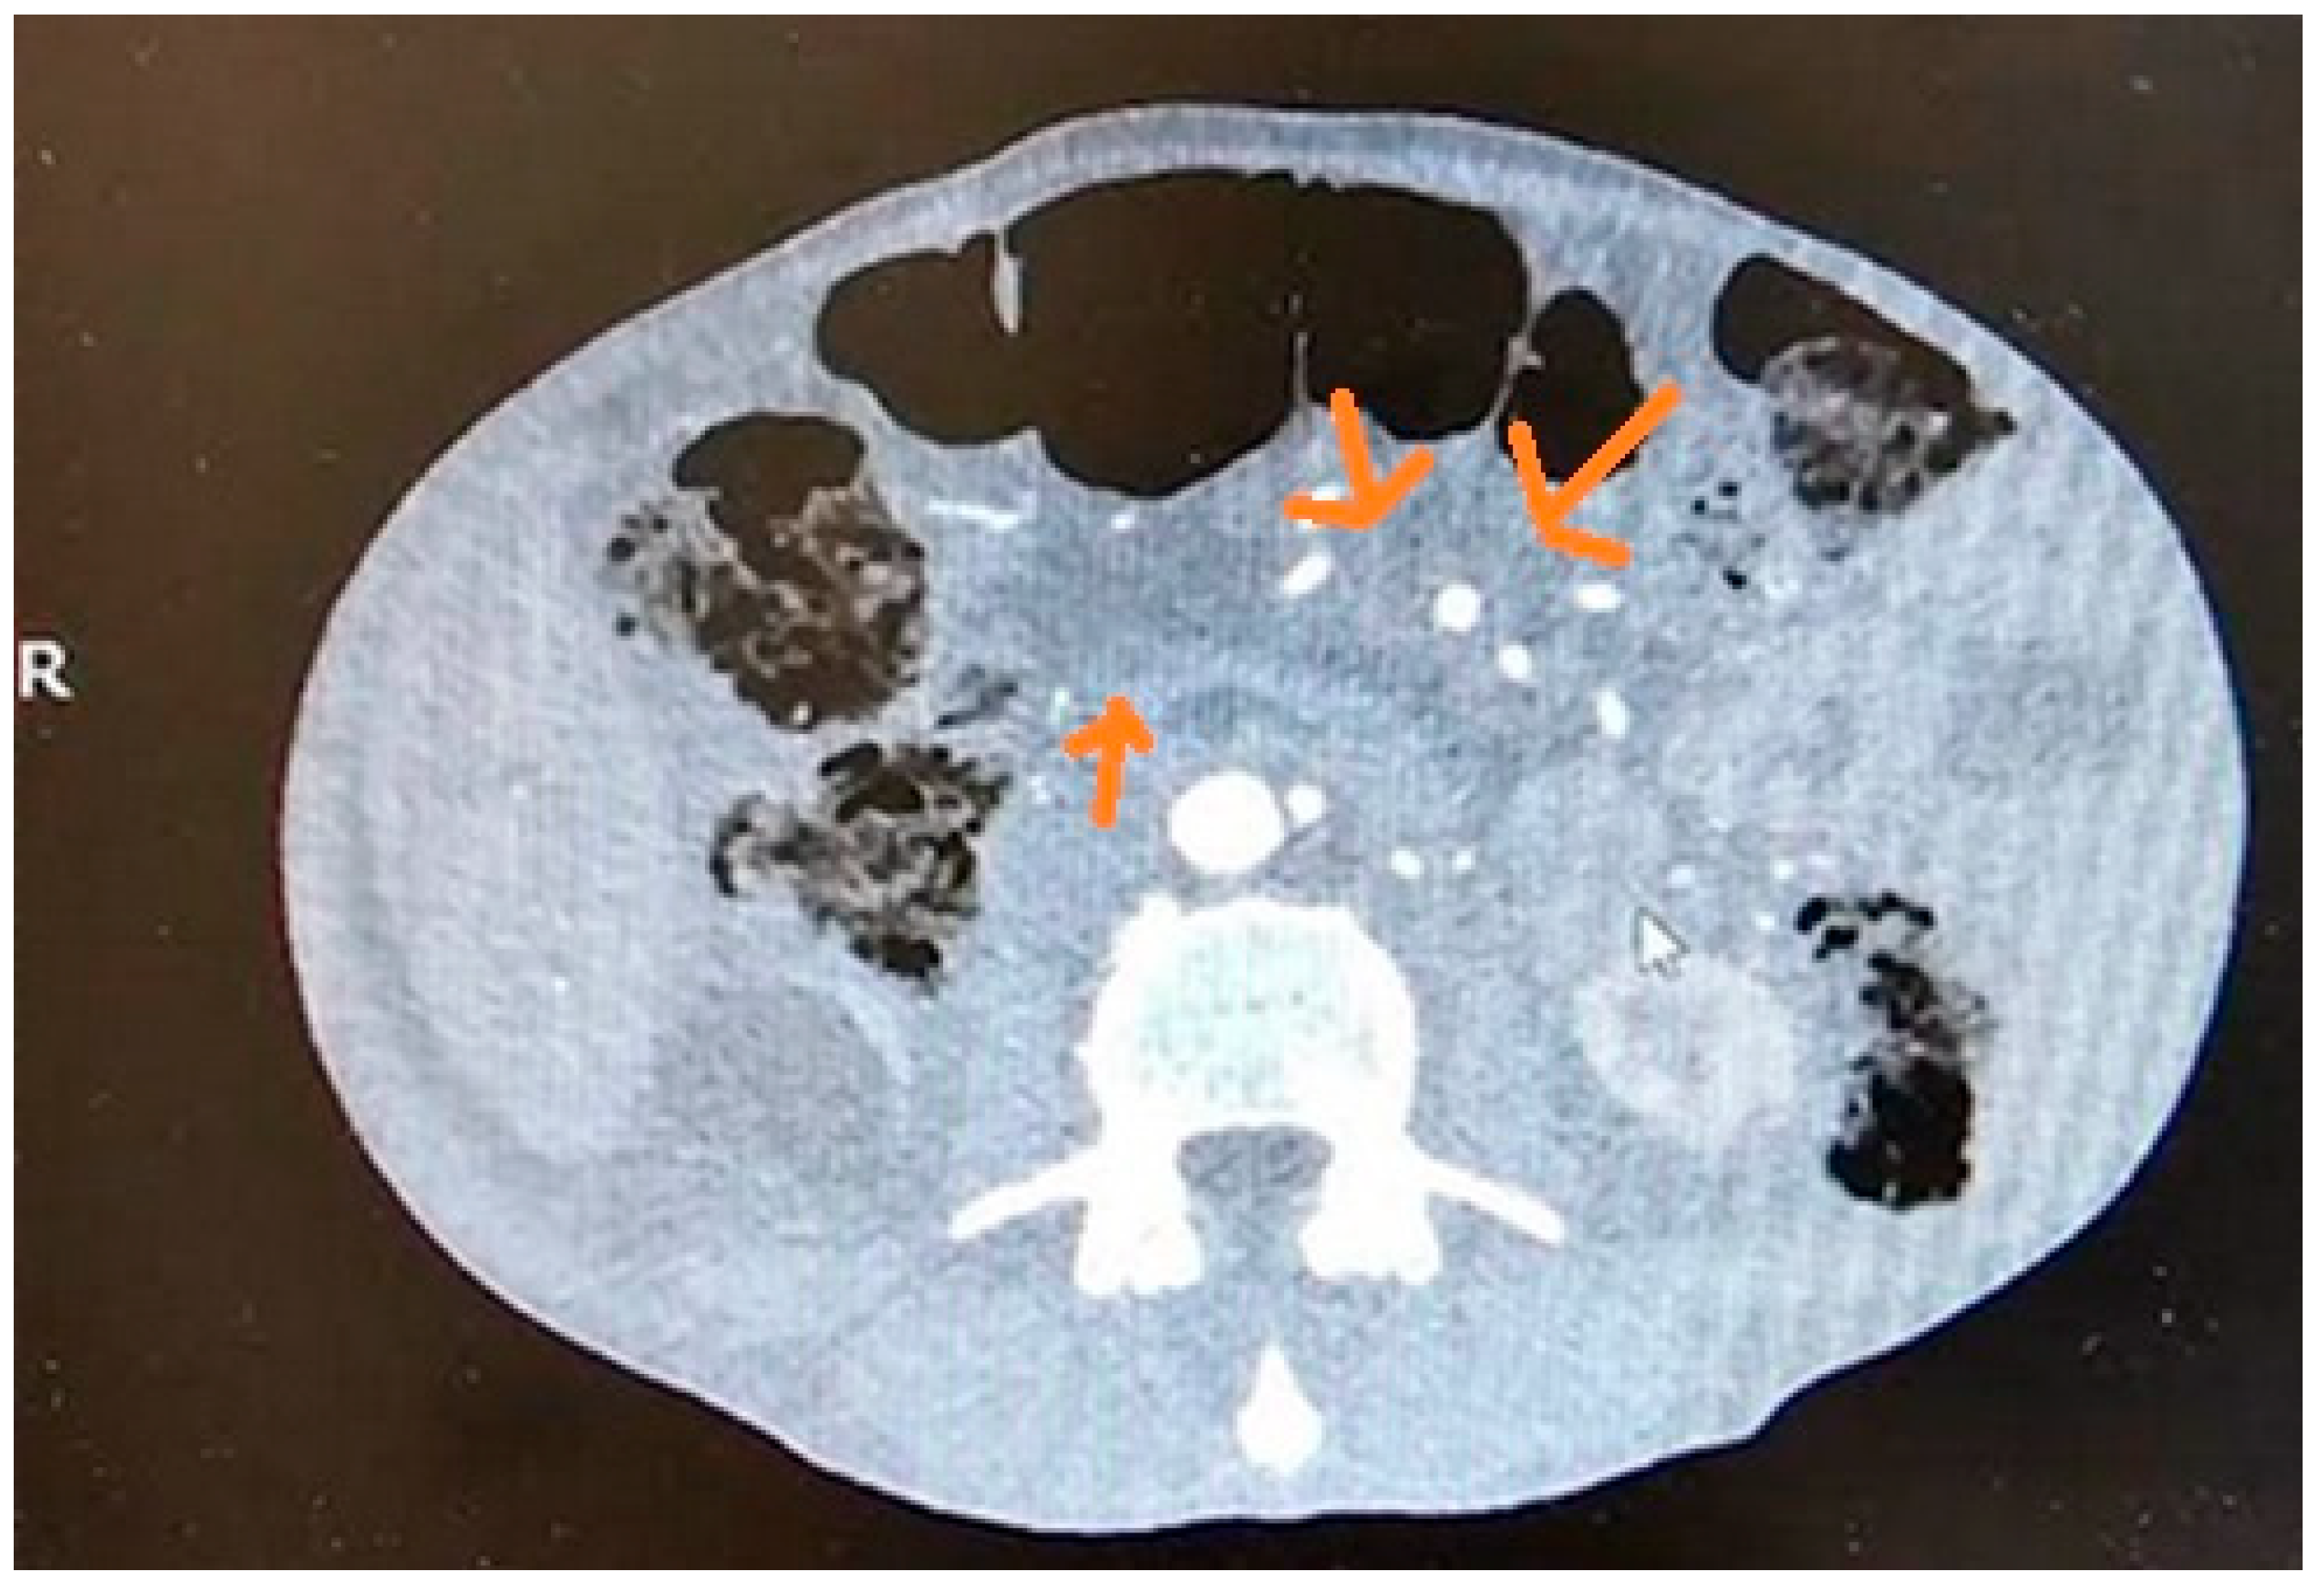

10.2. Computed Tomography (CT)